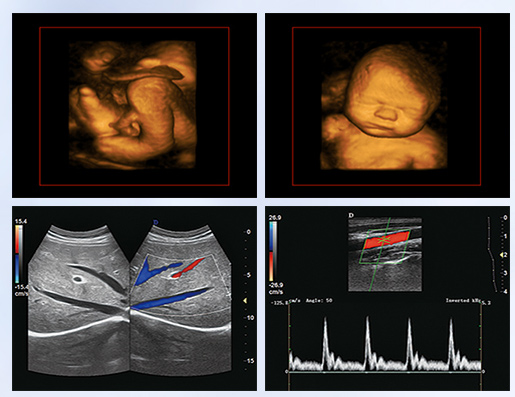

超聲學(xué)科的發(fā)展史,猶如一卷悠遠(yuǎn)綿長(zhǎng)的畫冊(cè)。從黑白B超機(jī)到彩超機(jī),從一維、二維向三維立體動(dòng)態(tài),從推車式B超機(jī)到便攜式彩超機(jī),從觀察人體解剖學(xué)到分析人體組織內(nèi)細(xì)微結(jié)構(gòu)和功能。隨著科學(xué)技術(shù)的不斷發(fā)展,B超機(jī)功能也越來(lái)越方便強(qiáng)大。

超聲作為一門醫(yī)、理、工相結(jié)合的學(xué)科,涵蓋超聲診斷、超聲治療和超聲工程技術(shù)等門類,其在臨床診斷和治療中發(fā)揮著日益重要的作用。B超機(jī)借助各種超聲探頭,以精湛的技術(shù)和嚴(yán)謹(jǐn)?shù)膽B(tài)度掃描著人體臟器內(nèi)的細(xì)微病變,給臨床提供準(zhǔn)確而快捷的檢查報(bào)告,在影影綽綽間,發(fā)現(xiàn)病魔的蛛絲馬跡中,用“金睛火眼”挽救患者性命……超聲的每一幅圖像,都是靠超聲醫(yī)生親自探查并采集的,每一個(gè)患者,至少都有10張以上的圖像存儲(chǔ),對(duì)于比較復(fù)雜的病例,有幾十甚至上百?gòu)垺6宜械膱D像,都需要超聲醫(yī)生在邊探查的時(shí)候,邊思考分析。這,是一個(gè)真正手腦并用的工作。